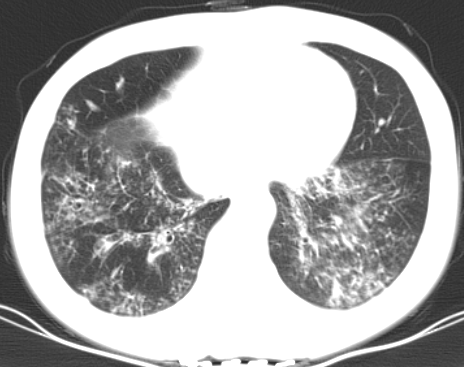

患者既往有“头孢”过敏史,余无特殊。入院后查体双下肺可闻及少量湿性啰音,余无阳性体征。胸部CT示:1.慢支,肺气肿;2.双肺感染性病变,双肺支扩;3.双侧胸膜增厚粘连。

图1 入院胸部CT

肺诺卡菌病常发生于全身或肺部局部免疫功能缺陷的宿主,临床症状主要表现为发热、咳嗽、咳痰等,影像学表现包括实变、结节、肿块及空洞等,肺部典型病理损害为坏死性脓肿,慢性感染者形成有肉芽肿。

该患者肺部CT提示患者既往有支气管扩张病史,再根据患者的临床症状、影像学改变及病原学检查结果支持肺诺卡菌病的诊断。根据该菌的药物敏感性调整用药,给予阿米卡星联合亚胺培南抗感染治疗,所使用诊断治疗方案符合热病中建议的治疗方案。治疗一周后复查CT,示双肺感染灶较前略显吸收好转,提示治疗有效。